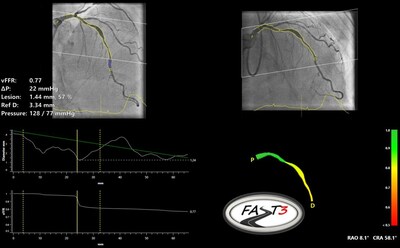

MAASTRICHT, Netherlands, June 18, 2024 /PRNewswire/ -- Pie Medical Imaging, a global leader in cardiac imaging, announced the completion of enrollment in FASTIII, a multi-center randomized clinical trial, which investigates the use of angiography-based vessel fractional flow reserve (CAAS vFFR) in patients undergoing coronary revascularization procedures. vFFR can assess whether a coronary artery narrowing is functionally significant and may require revascularization.

FASTIII is the largest non-inferiority trial running (having enrolled 2228 patients), in which an angiographically derived vFFR guided strategy is compared to a FFR guided strategy to guide coronary revascularization. The primary endpoint is a composite of all-cause death, any myocardial infarction, or any revascularization at 1-year post randomization.